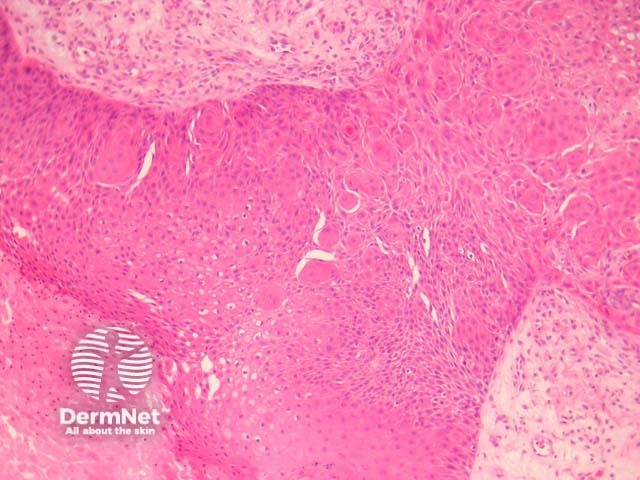

Sections show a cyst in the dermis with a proliferating epidermal component (figures 1, 2). Characteristically, the proliferative areas are made up of bland squamous epithelium with striking squamous eddies (figures 2, 3, 4). These eddies are whorles of maturing squamous epithelium and are exactly the same as those seen in irritated seborrheic keratoses or inverted follicular keratoses.

Figure 1

Figure 2